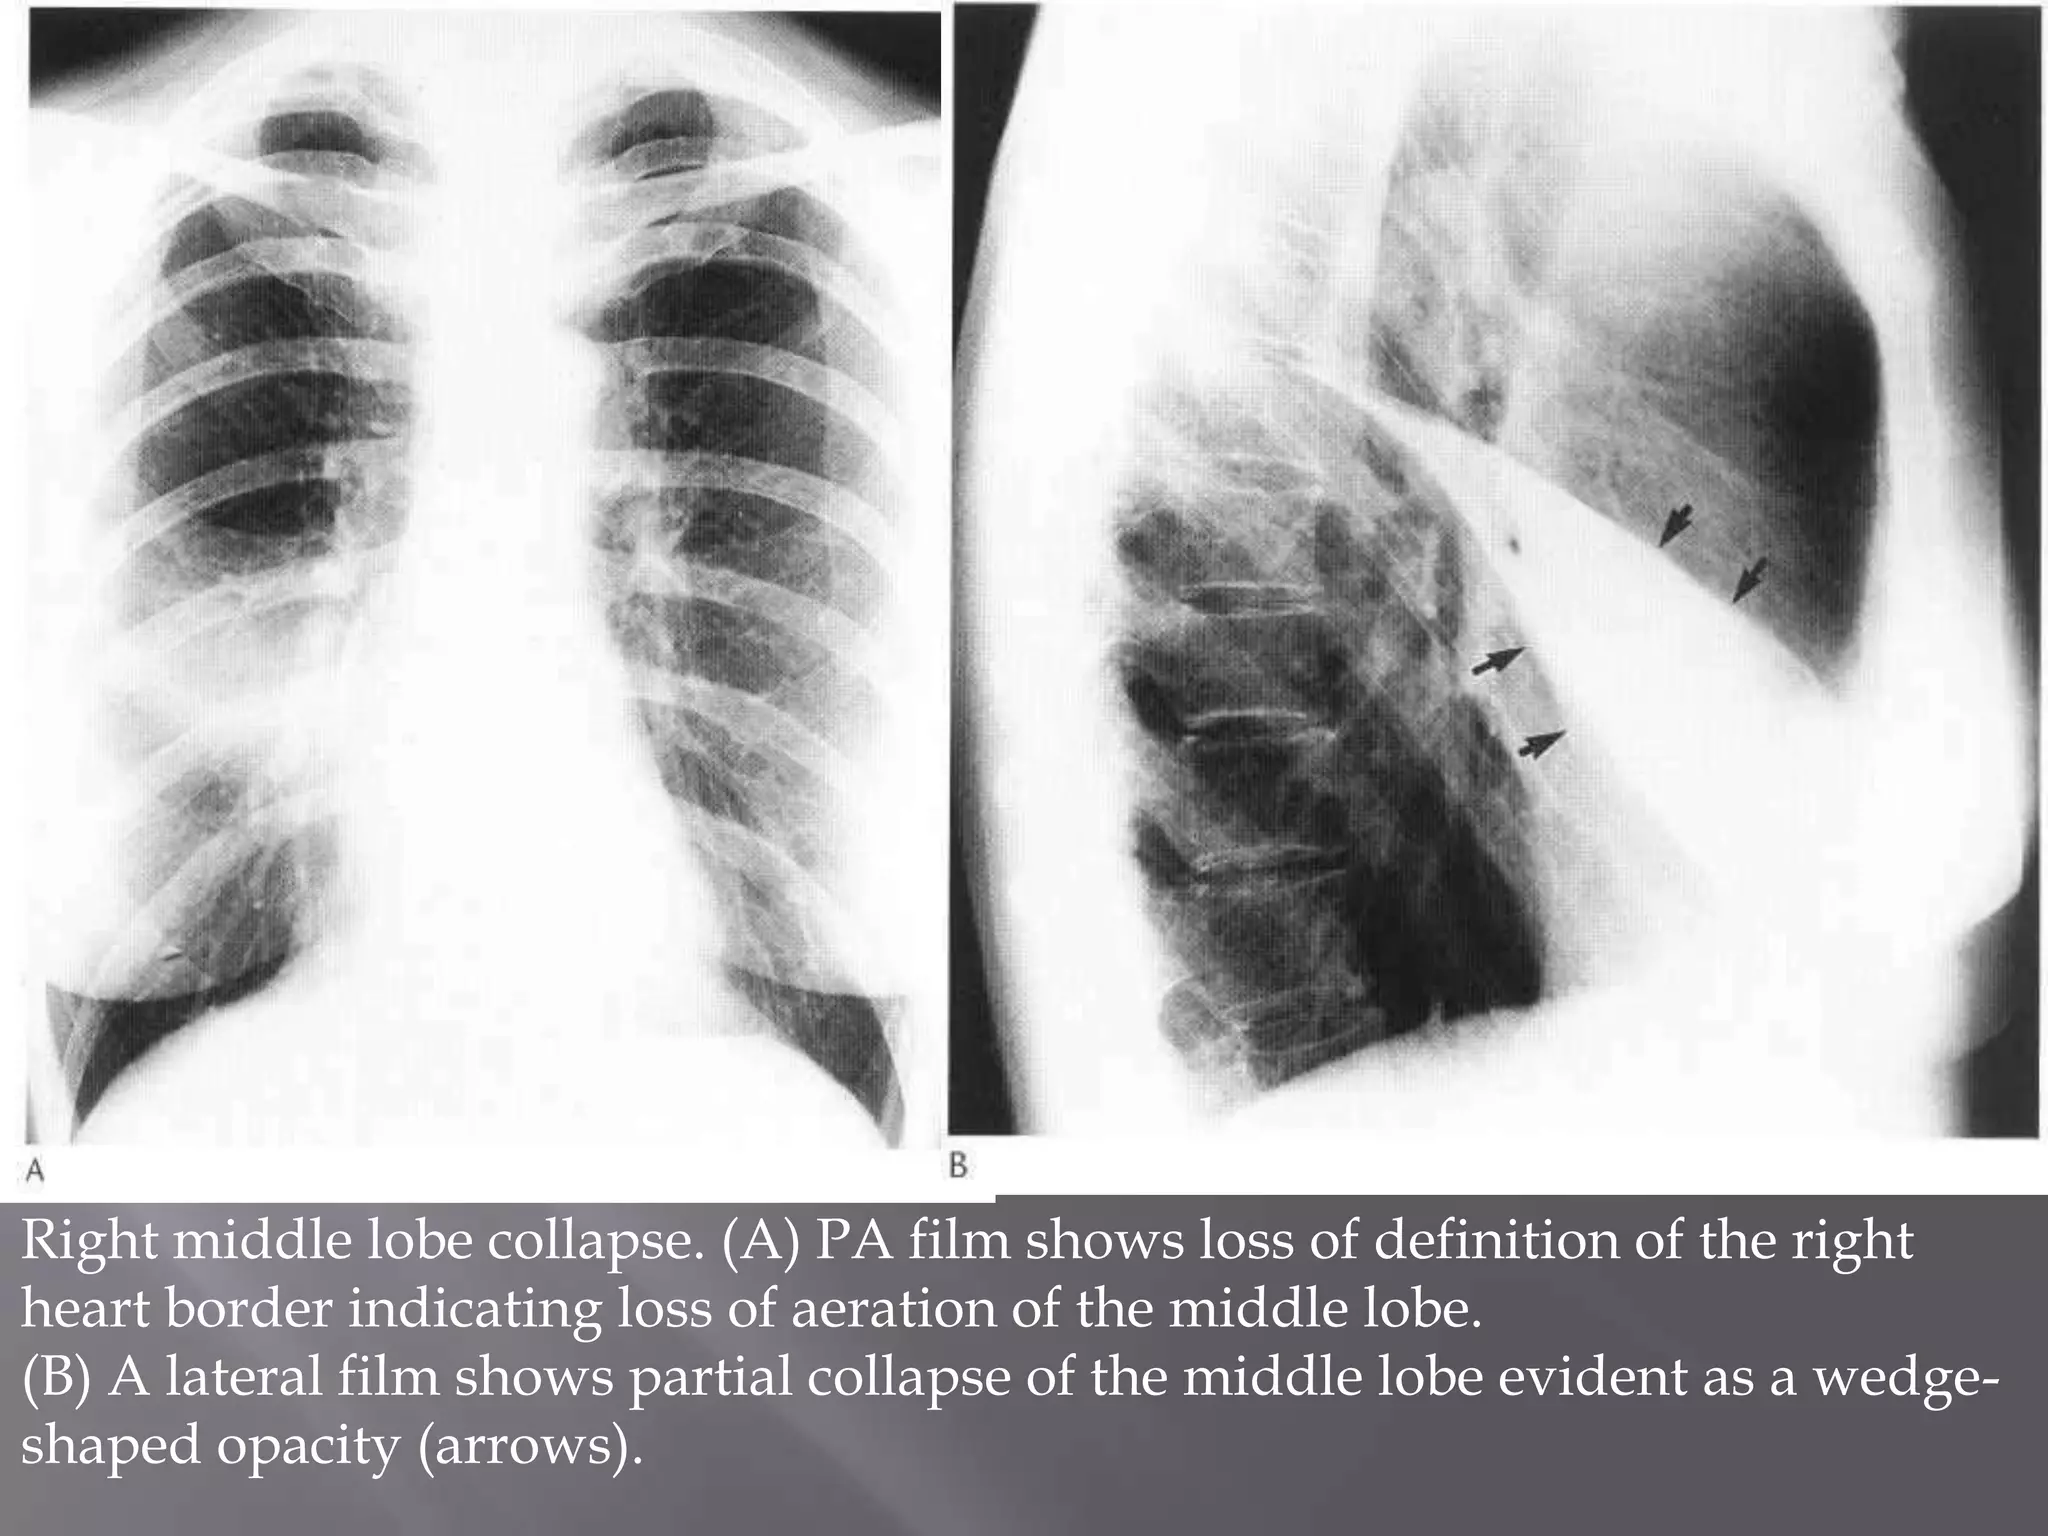

Right middle lobe collapse. (A) PA film shows loss of definition of the right

heart border indicating loss of aeration of the middle lobe.

(B) A lateral film shows partial collapse of the middle lobe evident as a wedge-

shaped opacity (arrows).

Right middle lobecollapse. (A) PA film shows loss of definition of the right heart border indicating loss of aeration of the middle lobe. (B) A lateral film shows partial collapse of the middle lobe evident as a wedge- shaped opacity (arrows).